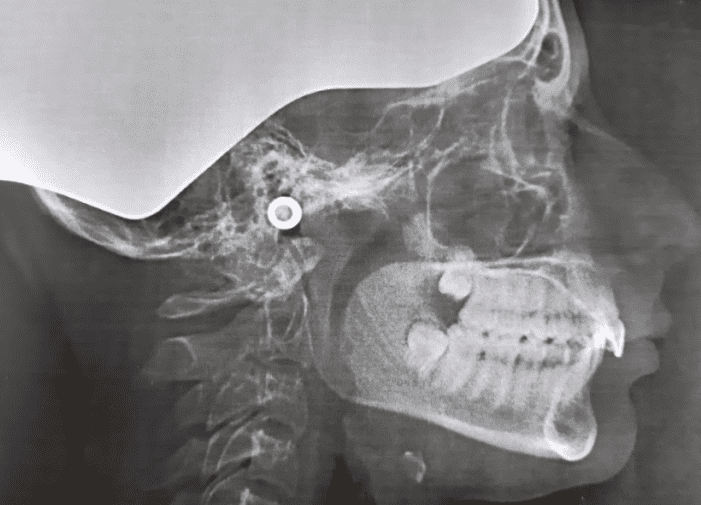

So i went to my Ortho today, and he gave me a twinblock. I asked him if it'll fuck with my maxilla and he kept kind of refusing to answer it properly he just said "it will change your side profile a tiny bit...." so me and my mom both agreed on looking into a surgical option. However could i get it with this kind of bite? And from what i read you will have to get braces and a wisdom tooth extraction before it, will that hurt my jaw?

My bite and Xray (dont mind the earbud)

My bite and Xray (dont mind the earbud)